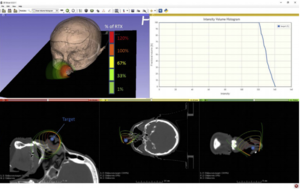

Evaluating the Utility of "3D Slicer" as a Fast and Independent Tool to Assess Intrafractional Organ Dose Variations in Gynecological Brachytherapy

Publication: Brachytherapy. 2016 Jul-Aug;15(4):514-23. PMID: 27180127 Authors: Siavashpour Z, Aghamiri MR, Jaberi R, Dehghan-Manshadi HR, Sedaghat M, Kirisits C. Institution: Department of Medical Radiation Engineering, Shahid Beheshti University, Tehran, Iran. Background/Purpose: To demonstrate the utility of 3D Slicer for easy treatment verification by comparing dose-volume histograms (DVHs) calculated on pretreatment and post-treatment images. Methods and Materials: Thirty cervical cancer patients were CT scanned twice: first for treatment planning and a second time after the dose delivery. The initial plan was manually duplicated on the post-treatment image set in Flexiplan treatment planning system, and DVH parameters were calculated. Pretreatment and post-treatment images, organ structures, and plan data were exported from the treatment planning system to 3D Slicer to validate DVH parameter calculation with 3D Slicer. The gamma analysis was used to compare Flexiplan and 3D Slicer DVHs. Post-treatment images were rigidly fused on the initial CT to automatically transfer the data of the pretreatment plan onto the post-treatment images. DVH parameters were calculated in 3D Slicer for both image sets, and their relative variations were compared. Results: In calculating DVH parameter variations, no significant differences were observed between Flexiplan and 3D Slicer. Where the registration accuracy was better than 0.03, they returned similar results for D2 cm3 of bladder, rectum, and sigmoid. Mean and standard deviation of DVH parameters were calculated on pretreatment and posttreatment images for several organs; both the manually duplicated plan and the automatically registered plan in SlicerRT returned comparable relative variations of these parameters. For 88% of the organs, more than 95% of the DVH dose bins passed the gamma analysis. Conclusions: We tested an automated DVH assessment method with an imaging freeware, 3D Slicer, for use in image-guided adaptive brachytherapy. SlicerRT is a viable verification tool to report and detect DVH variations between different contoured images series. |